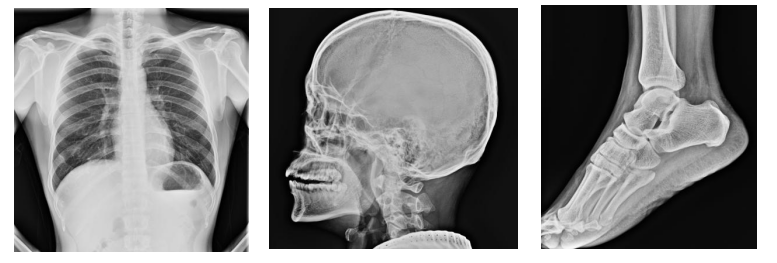

七、体检现场剪影:

体检车可实现,现场问诊,身体数据采集(身高、体重、三围、血压),监测数据采集存储(X光、B超、心电图),生化采样(血常规、尿常规、血糖、乙肝5项)。其中搭载了移动通讯装备的体检车,还能实现远程医疗会诊,可用于现场体检、简易治疗,是一个移动体检**和流动诊所。

内部分为登记区、体检区、休息区等,合理布局,配置同体检相关设备和生活****,完成正常健康体检和职业病检查等,功能齐全。